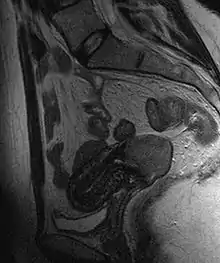

Often before the biopsy, the doctor asks for medical imaging to rule out other causes of woman's symptoms. Imaging modalities such as ultrasound, CT scan, and MRI have been used to look for alternating disease, spread of the tumor, and effect on adjacent structures. Typically, they appear as heterogeneous mass on the cervix.[49]